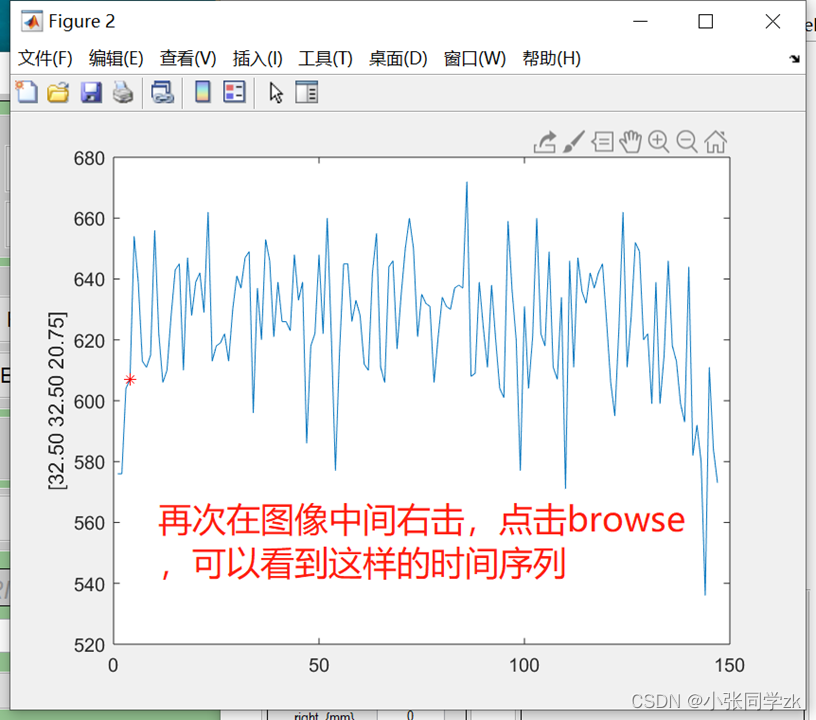

按照下图,点击Display,同样功能像也可以这样加进去,我们还可以看每个被试的时间序列信息

观察功能像: